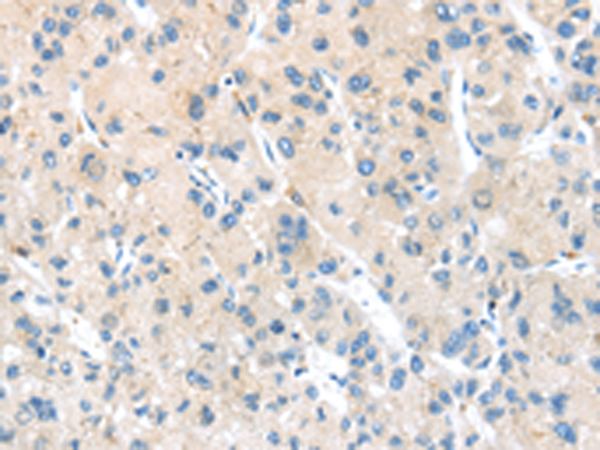

分类: 科研抗体货号: P11830别名: DP5; HARAKIRI应用: IHC反应种属: Human